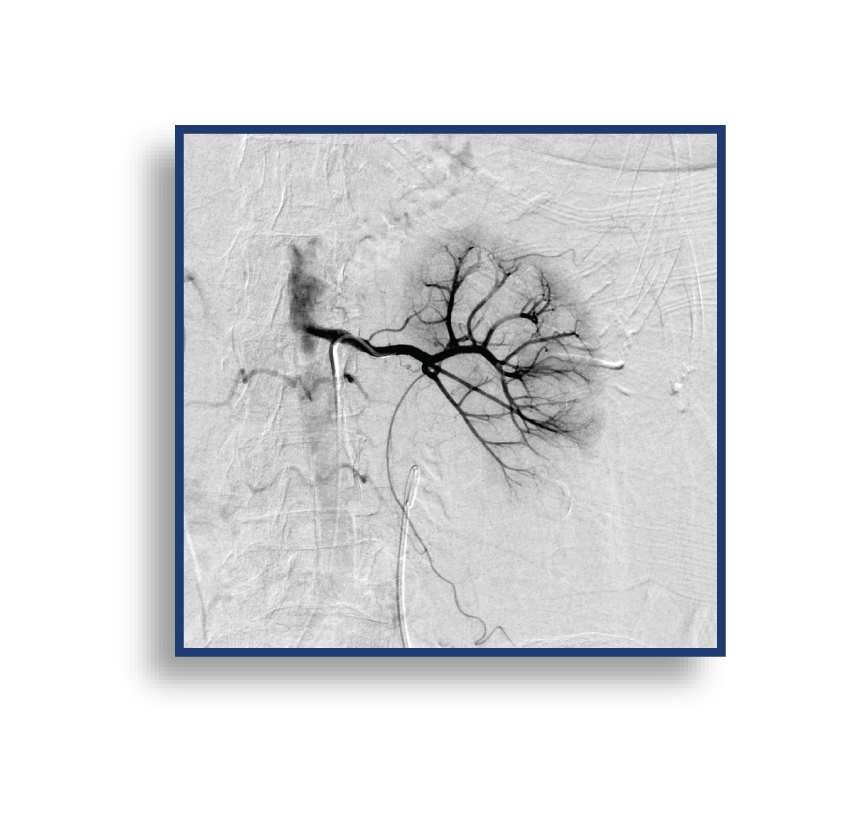

The LAVA Liquid Embolic System (LES) is The First and Only Liquid Embolic Approved for Peripheral Arterial Hemorrhage.

LAVA provides the confidence to quickly stop bleeds results in controlled target vessel occlusion.

LAVA is available in a 2 mL vial and a 6 mL vial; both vials have an 18 or 34 viscosity option. These pre-mixed vials allow for both a proximal target embolization and a distal target embolization, providing options to reach the bleed. The 2 mL LAVA LES comes with two (2) 1 mL delivery syringes and the 6 mL LAVA LES offers six (6) 1 mL delivery syringes, enabling you multi-zone embolization options from 1 pre-mixed vial. An optional Mixing Kit is available to expedite the shaking of the vial, which suspends the radiopaque particles. The volume of the particles in LAVA has been designed to reduce flash for clear imaging.